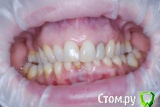

VVQW Опубликовано 6 декабря, 2016 Поделиться Опубликовано 6 декабря, 2016 (изменено) Более 10 лет назад была установлена брекет-система.Лечение было проведено на глаз, анализы и диагностика не проводилась. Спустя время- итог. Сверху перед установкой врач принял решение удалить 6-ки, 8-ки -не выросли. Промежутки между 7-ми и 5-ми - не дотянул и бросил врач. На нижней челюсти системы не было, нижние 6-ки потеряны лет до 14 (в подростковом возрасте). Сейчас процес -усугубляются клиновидки, оголение . Что можно сделать? http://s019.radikal.ru/i641/1612/eb/3498e6cec3f8.jpg http://s018.radikal.ru/i518/1612/73/739600b6d2d1.jpg http://s011.radikal.ru/i318/1612/73/443e1513aaf8.jpg http://s017.radikal.ru/i403/1612/86/73e0dfe4ca62.jpg http://s018.radikal.ru/i518/1612/a2/bd7078537d9e.jpg http://s017.radikal.ru/i417/1612/9d/41b6d1c98666.jpg http://s019.radikal.ru/i642/1612/fe/3222fa19d517.jpg Гипсовых моделей нет, зубы неподвижны. http://s019.radikal.ru/i639/1612/56/1345f17db908.jpg http://s019.radikal.ru/i630/1612/55/145ef7c813b2.jpg http://s017.radikal.ru/i440/1612/c2/74bd4da2643e.jpg http://s008.radikal.ru/i303/1612/b4/e80683ed7d2b.jpg http://s010.radikal.ru/i314/1612/74/6d2f9671b0d5.jpg http://s018.radikal.ru/i502/1612/97/9a15fcf4ddd3.jpg http://s020.radikal.ru/i715/1612/59/9bb4a006621f.jpg Изменено 6 декабря, 2016 пользователем VVQW Ссылка на комментарий